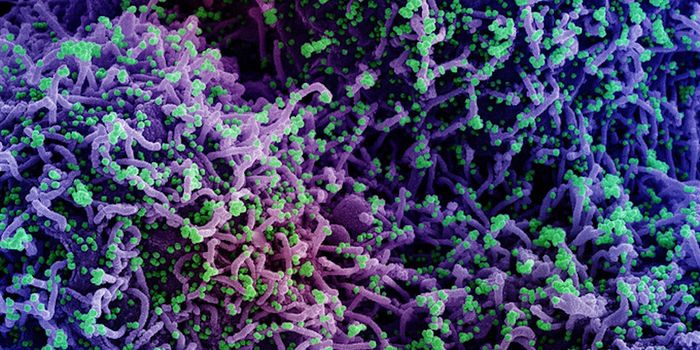

MAY 10, 2021MicrobiologyThe pandemic virus SARS-CoV-2 has changed the world in devastating ways, taking hundreds of thousands of lives & new var ...